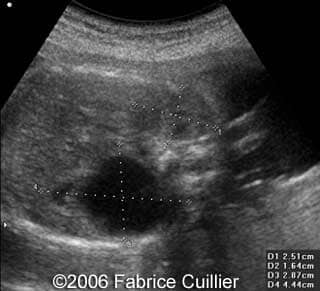

• an abnormal polycystic left kidney (34 X 17 mm) with an abnormal corticomedullar differentiation. This kidney was on the lumbar fossa.

Note the large cyst